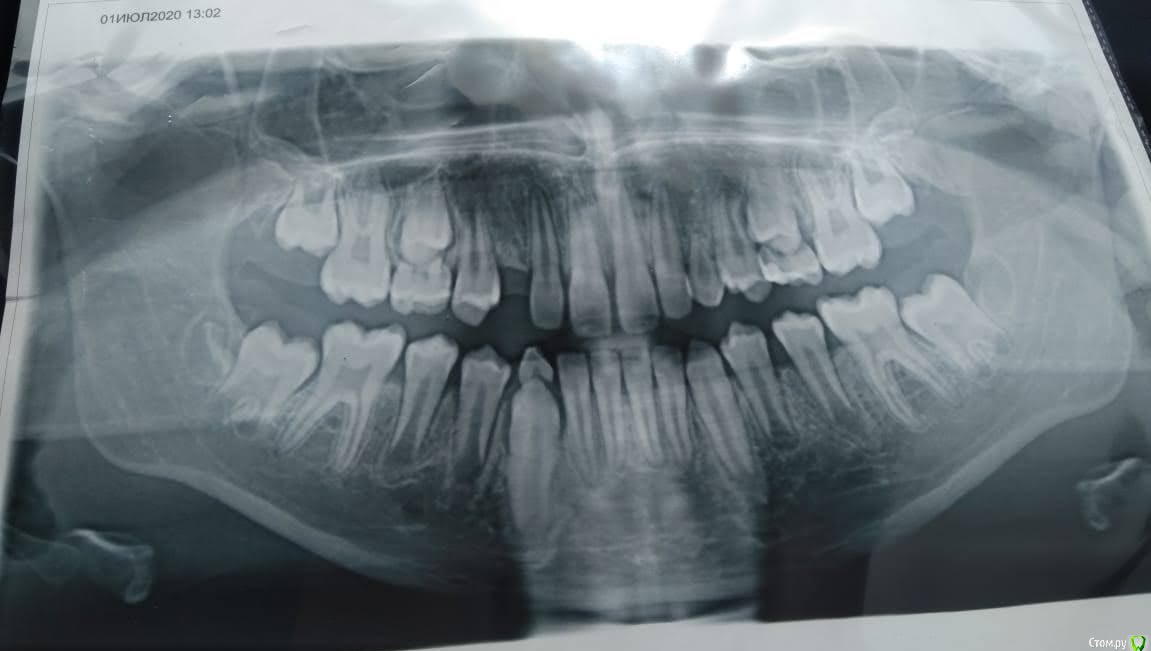

Леля1983 Опубликовано 21 июля, 2020 Поделиться Опубликовано 21 июля, 2020 (изменено) Добрый день. Ребенку 10 лет. Сделали ортопантомограмму. На ней нет зачатков верхних коренных клыков. У отца ребенка верхний клык вырос в нёбе, и до 30 лет он ходил с молочным зубом. Обнаружить зуб удалось только на КТ (3 d). Необходимо ли ребенку делать дополнительное обследование в виде КТ? У ортодонта были. К сожалению, такой практики у него не было и лечение , доп обследование не назначил. Записались к другому. Может ли быть такое, что на ортопантомограмме не все видно? Изменено 21 июля, 2020 пользователем Леля1983 1 Ссылка на комментарий

Леля1983 Опубликовано 22 июля, 2020 Автор Поделиться Опубликовано 22 июля, 2020 Снимок Ссылка на комментарий

kramer Опубликовано 22 июля, 2020 Поделиться Опубликовано 22 июля, 2020 Верхних клыков нет и не будет, до плюс/минус 20 лет нужно будет что-то временное для их замены, потом имплантация Ссылка на комментарий

Леля1983 Опубликовано 22 июля, 2020 Автор Поделиться Опубликовано 22 июля, 2020 Верхних клыков нет и не будет, до плюс/минус 20 лет нужно будет что-то временное для их замены, потом имплантация Спасибо большое за ответ. Сейчас пытаемся найти ортодонта, который внятно смог бы объяснить что в нашем случае "временное" приемлемо. Ссылка на комментарий